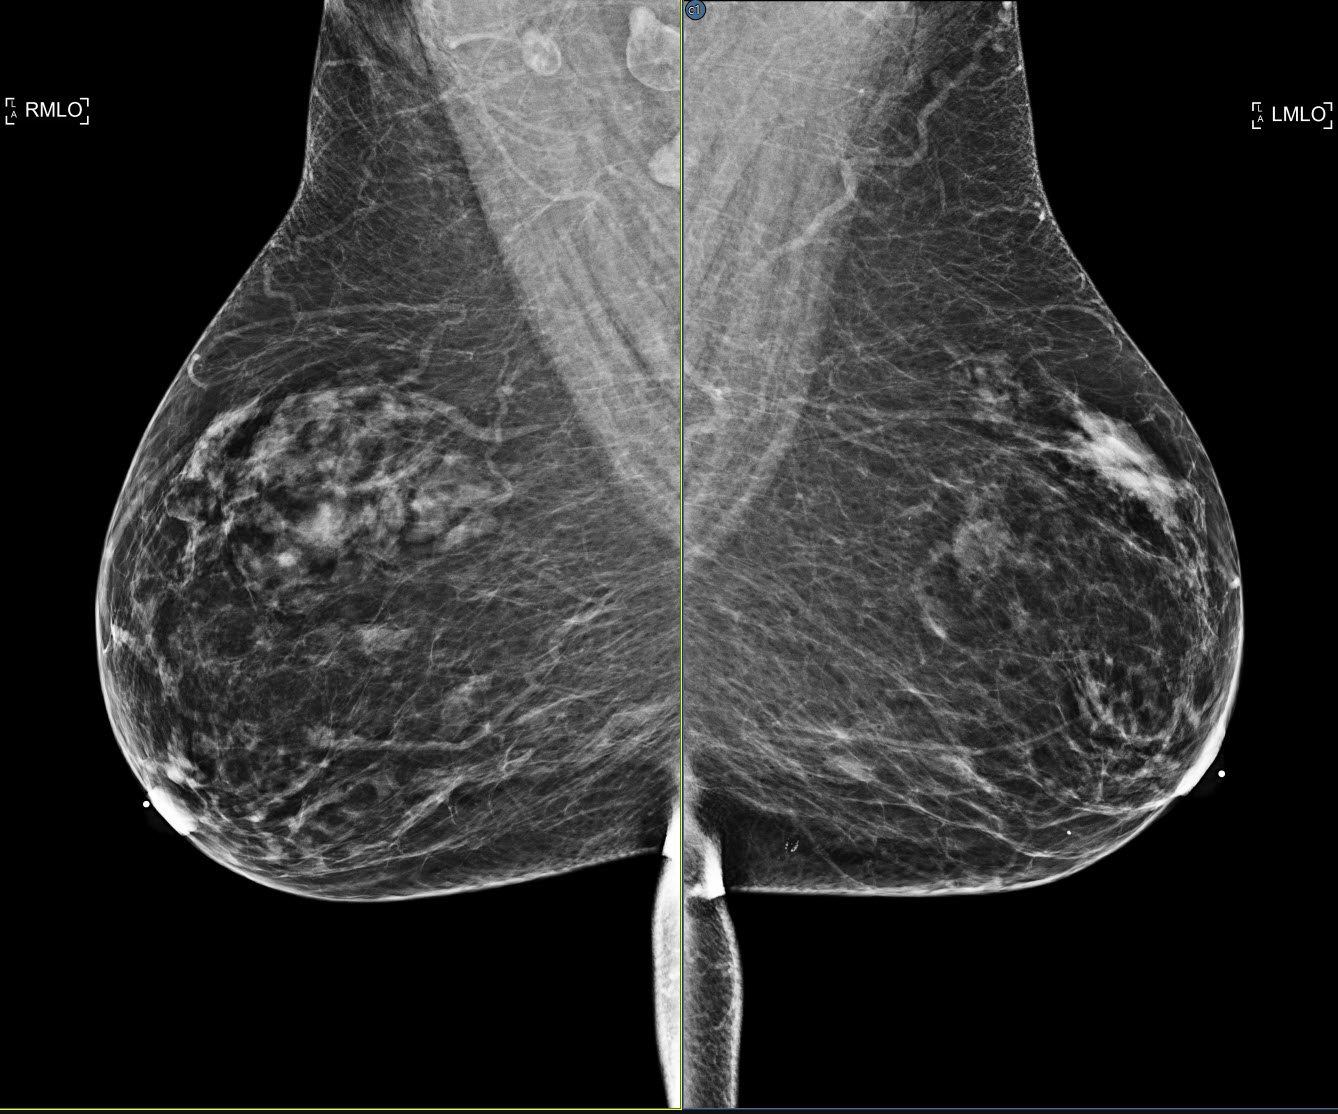

The viewer supports the DeepHealth Saige-Density SR objects, displaying the case density score in the CAD header and, optionally, in the overlay data using the Breast Composition info tag.

Additional information from iCAD SR objects is displayed, including the case score and case score label in the CAD header. If synthetic 2D images and BTO series are present in the same study, cross correlation is enabled allowing the user to jump to the tomo slice corresponding to the location selected. Lastly, the graphic icons used to represent iCAD calcification clusters (rotated square) and masses (ellipse) have been updated.

DeepHealth CAD suspicion levels are indicated in the finding icon in the stack ruler. One to three lines indicate low, medium and high suspicion levels, respectively. No line indicates no suspicion level defined in the CAD object. Additionally, if the CAD object defines a color for the finding markers, the color is applied to the graphics in the image and stack ruler. This feature can be disabled from the Use color for CAD markers setting on the Options/Presentation States/Mammography CAD SR settings page.

The viewer supports ScreenPoint’s Transpara CAD objects.

The CAD header with the Transpara logo contains the number of calcification and mass findinds, the algorithm version and the Transpara score (integer value between 0 and 10).

Calcifications are marked by a diamond outline and the contour of individual calcifications.

Masses are marked by their contour (plus the default marker if enabled).

There’s an additional type of finding for Screenpoint called “decision support”, which describes a more general region of interest. So far, Transpara is the only CAD that uses this type but this might change in the future. In order to have a more general tool, the viewer refers to this type of finding as “region of interest”.

A new option has been added to both the global and local CAD menu to show/hide regions of interest. The default is off.

In case of Transpara, regions of interest appear as color-coded circles that usually - but not always - have a score associated with them.

Support for DeepHealth Saige-Q SR objects has been added. The triage header displays the algorithm name and version, and the case assessment type and value.

A new setting that enhances the viewer's SmartFit zoom capability by identifying anatomy that is not breast and excluding it from the normal SmartFit calculations. The data remains available by panning the image. The setting is disabled by default. The feature can be enabled from the Enhanced Smart Fit setting in the Images/Zoom section of the viewer settings panel. See Images

| Enabled | Disabled |

Added support for Hologic's Genius AI™ objects.

Genius AI™ Detection* (* pending FDA clearance) is a software module intended to identify suspicious breast lesions appearing as soft-tissue densities (masses, architectural distortions, and asymmetries) or calcification clusters in Hologic Selenia Dimensions breast tomosynthesis images, using deep learning neural networks.

See Cross_Correlate_2D_CAD_in_Tomosynthesis_Images and CAD_Certainty_Scores

Added support for DeepHealth's updated CAD objects in which findings marked in 2D images are correlated to a position in a specific BTO frame or frames. See Cross_Correlate_2D_CAD_in_Tomosynthesis_Images